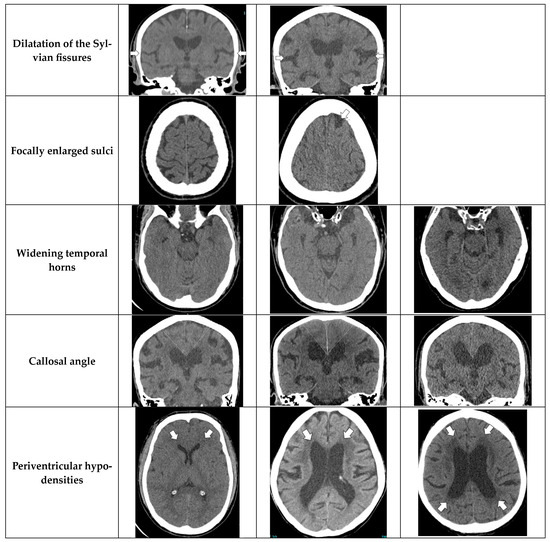

Diagnostics Free FullText The Diagnostic Accuracy of Artificial